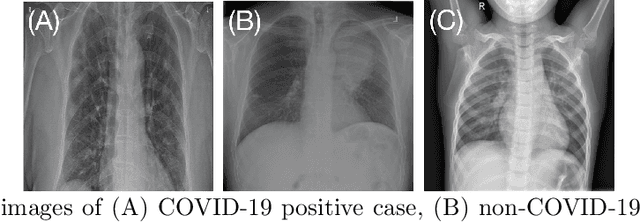

Abstract:Deep learning (DL) techniques have been extensively utilized for medical image classification. Most DL-based classification networks are generally structured hierarchically and optimized through the minimization of a single loss function measured at the end of the networks. However, such a single loss design could potentially lead to optimization of one specific value of interest but fail to leverage informative features from intermediate layers that might benefit classification performance and reduce the risk of overfitting. Recently, auxiliary convolutional neural networks (AuxCNNs) have been employed on top of traditional classification networks to facilitate the training of intermediate layers to improve classification performance and robustness. In this study, we proposed an adversarial learning-based AuxCNN to support the training of deep neural networks for medical image classification. Two main innovations were adopted in our AuxCNN classification framework. First, the proposed AuxCNN architecture includes an image generator and an image discriminator for extracting more informative image features for medical image classification, motivated by the concept of generative adversarial network (GAN) and its impressive ability in approximating target data distribution. Second, a hybrid loss function is designed to guide the model training by incorporating different objectives of the classification network and AuxCNN to reduce overfitting. Comprehensive experimental studies demonstrated the superior classification performance of the proposed model. The effect of the network-related factors on classification performance was investigated.